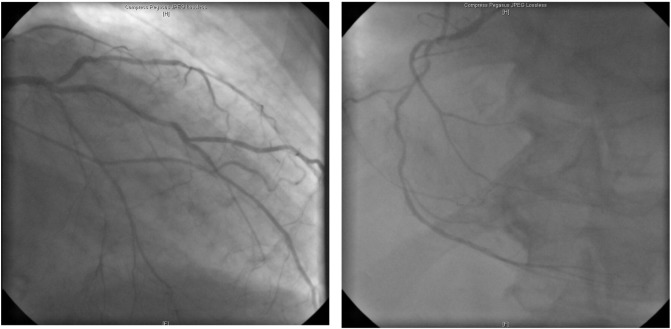

Coronary angiogram shows a three-vessel coronary artery disease. (A) Left ...

Coronary angiogram shows a three-vessel coronary artery disease. (A) Left coronary angiogram shows critical stenosis of LAD in the middle segment and ostial occlusion of the LCA with collateral perfusion through the LAD. (B) Right coronary angiogram shows proximal and distal critical stenosis of the right coronary artery, RD1 and RIM.